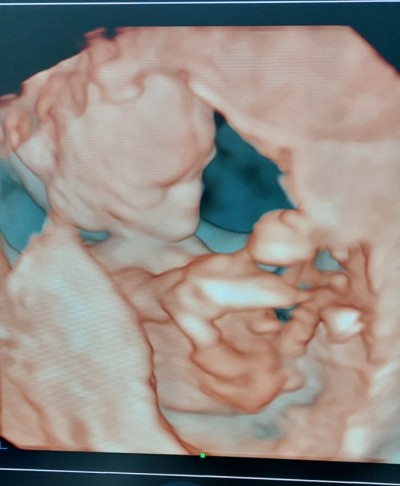

Merhaba hanımlar dün doktor kontrolünde kesin değil haftaya net söylerim ama erkek gibi duruyor dedi sizce cinsiyeti nedir

Gebelik haftası 15

Bana da erkek gibi geldi bacağının arasından geçen kordonu değilse tabi :)

Bence erkek annesi :)

Erkek sanırım bacak arası dolu gibi